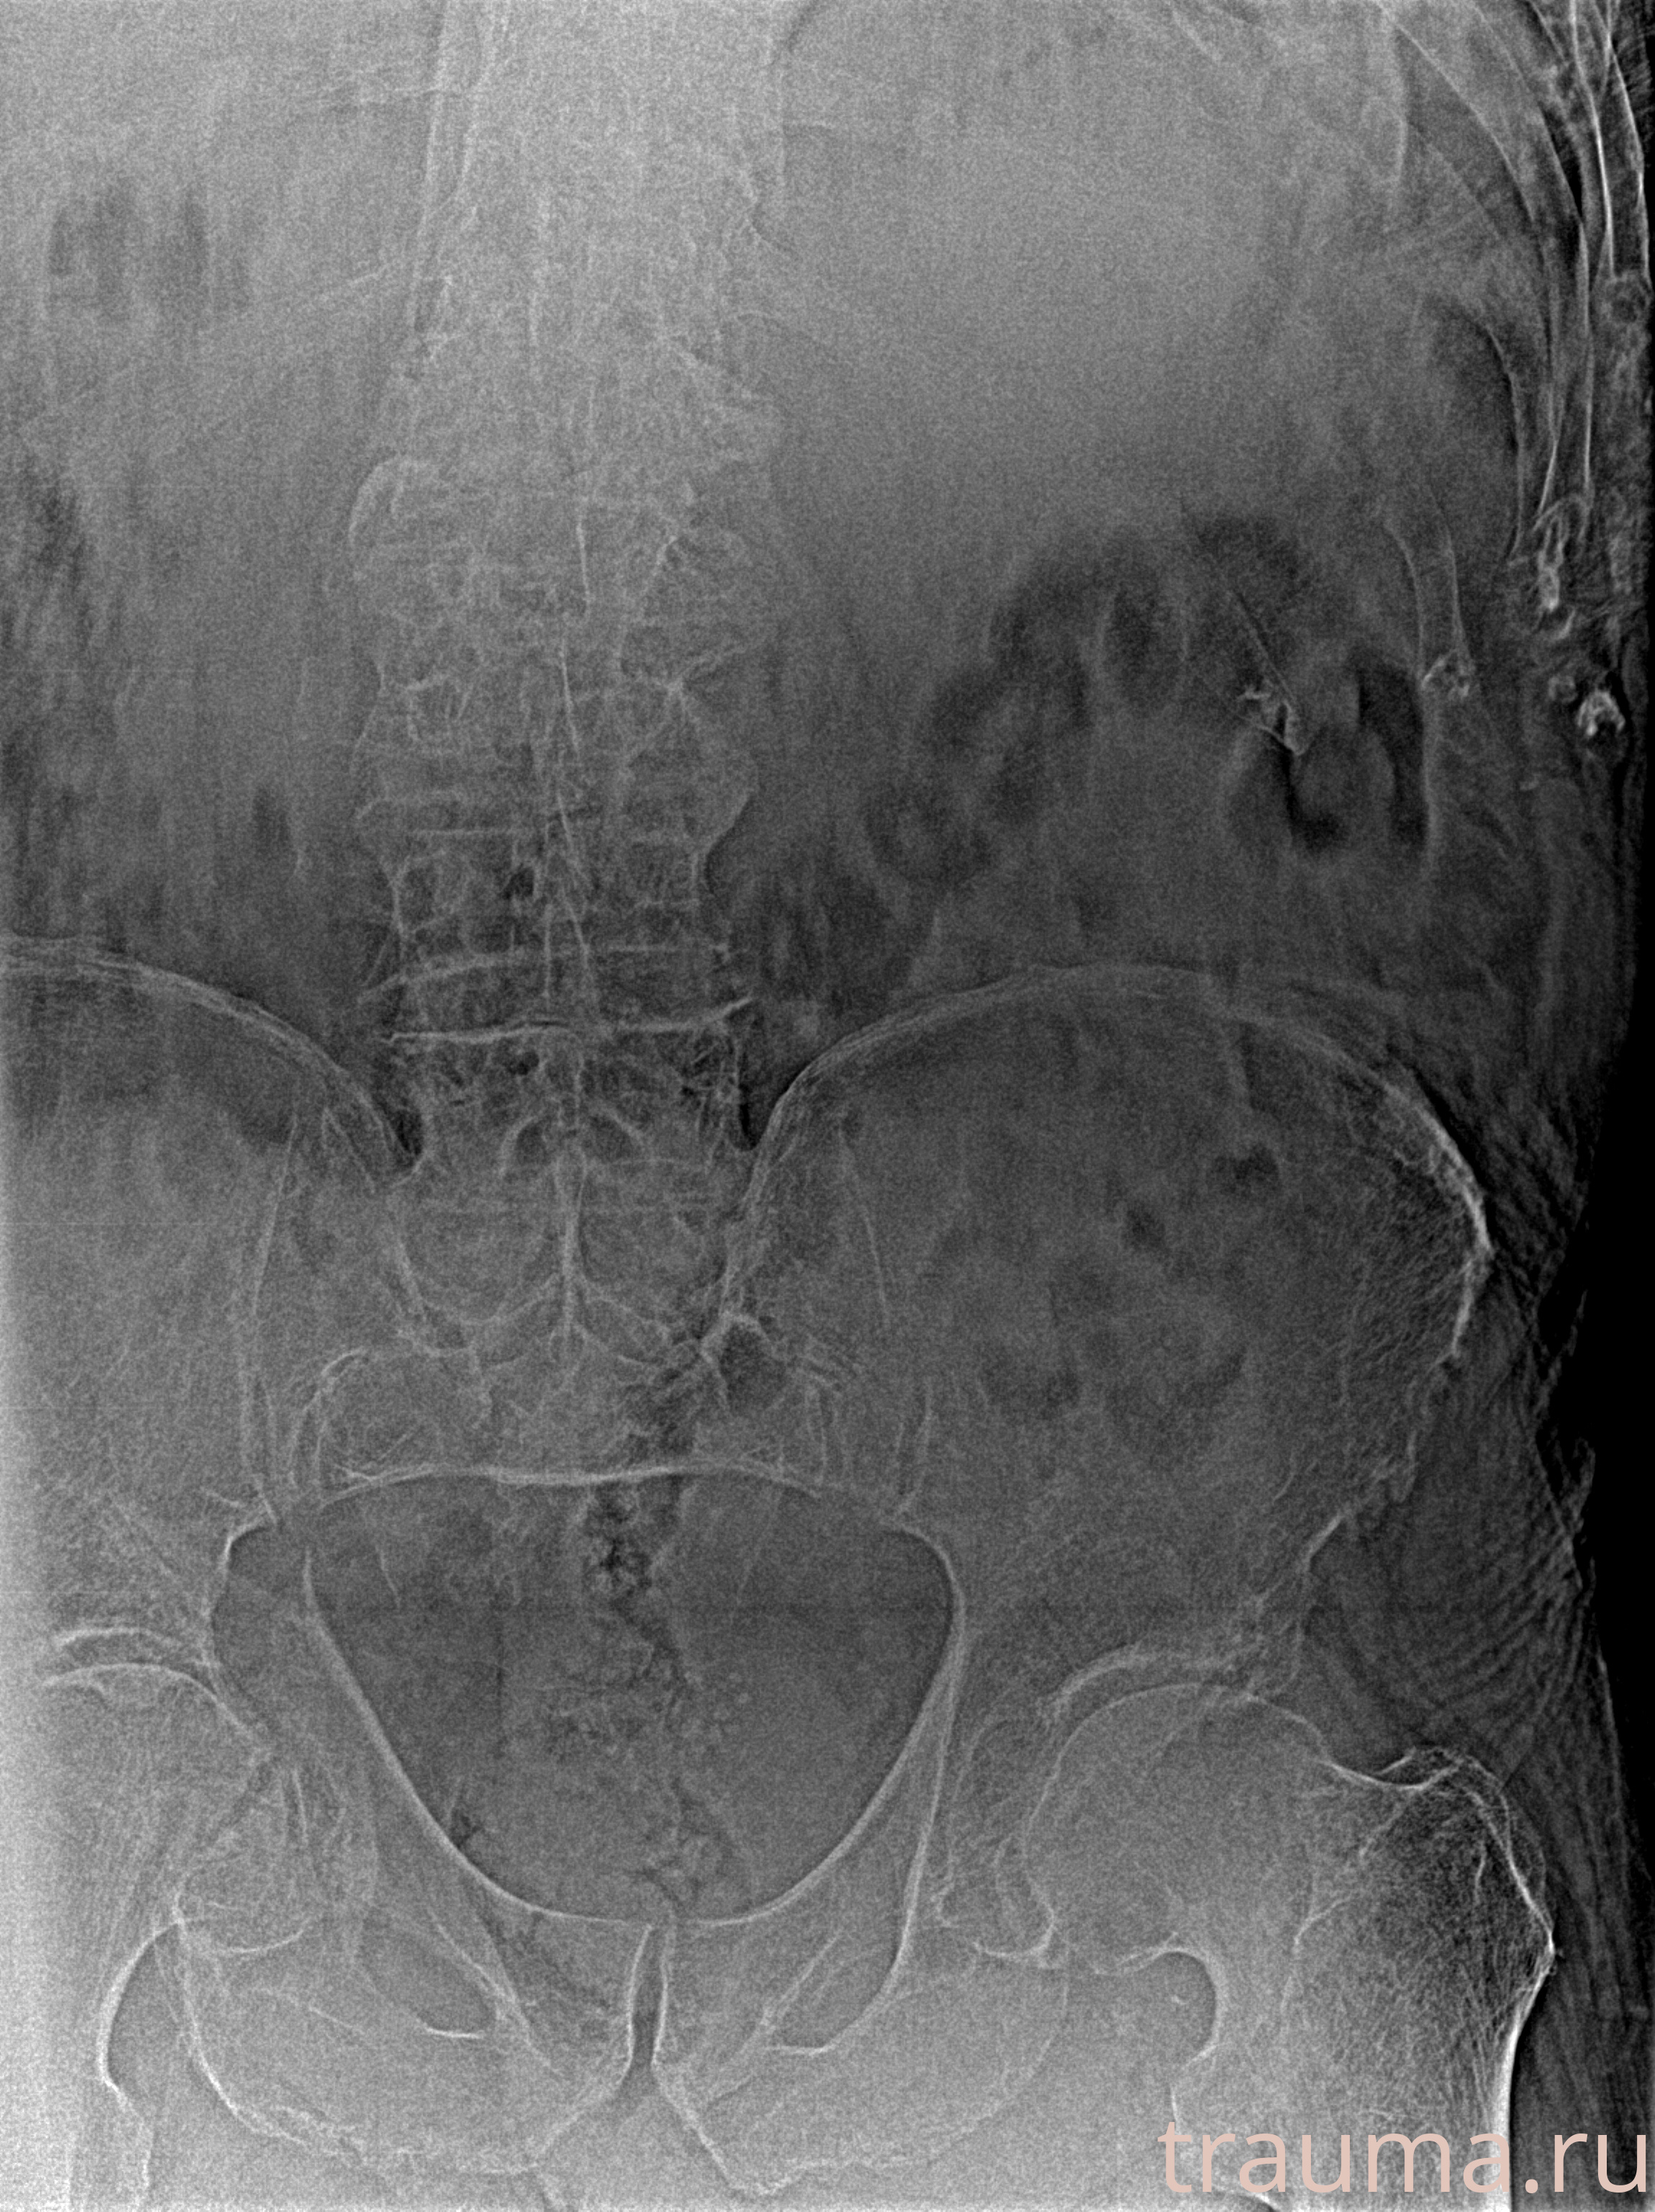

Рентгенограммы

Рентген на дому: по вашему адресу приезжает врач-рентгенолог, травматолог-ортопед с мобильным рентгеновским аппаратом, проводит диагностику травмы или заболевания, делает необходимые рентгенограммы, дает рекомендации по дальнейшему лечению. Получить качественные снимки в домашних условиях возможно благодаря уникальной методике, разработанной МосРентген Центром для института  Склифосовского